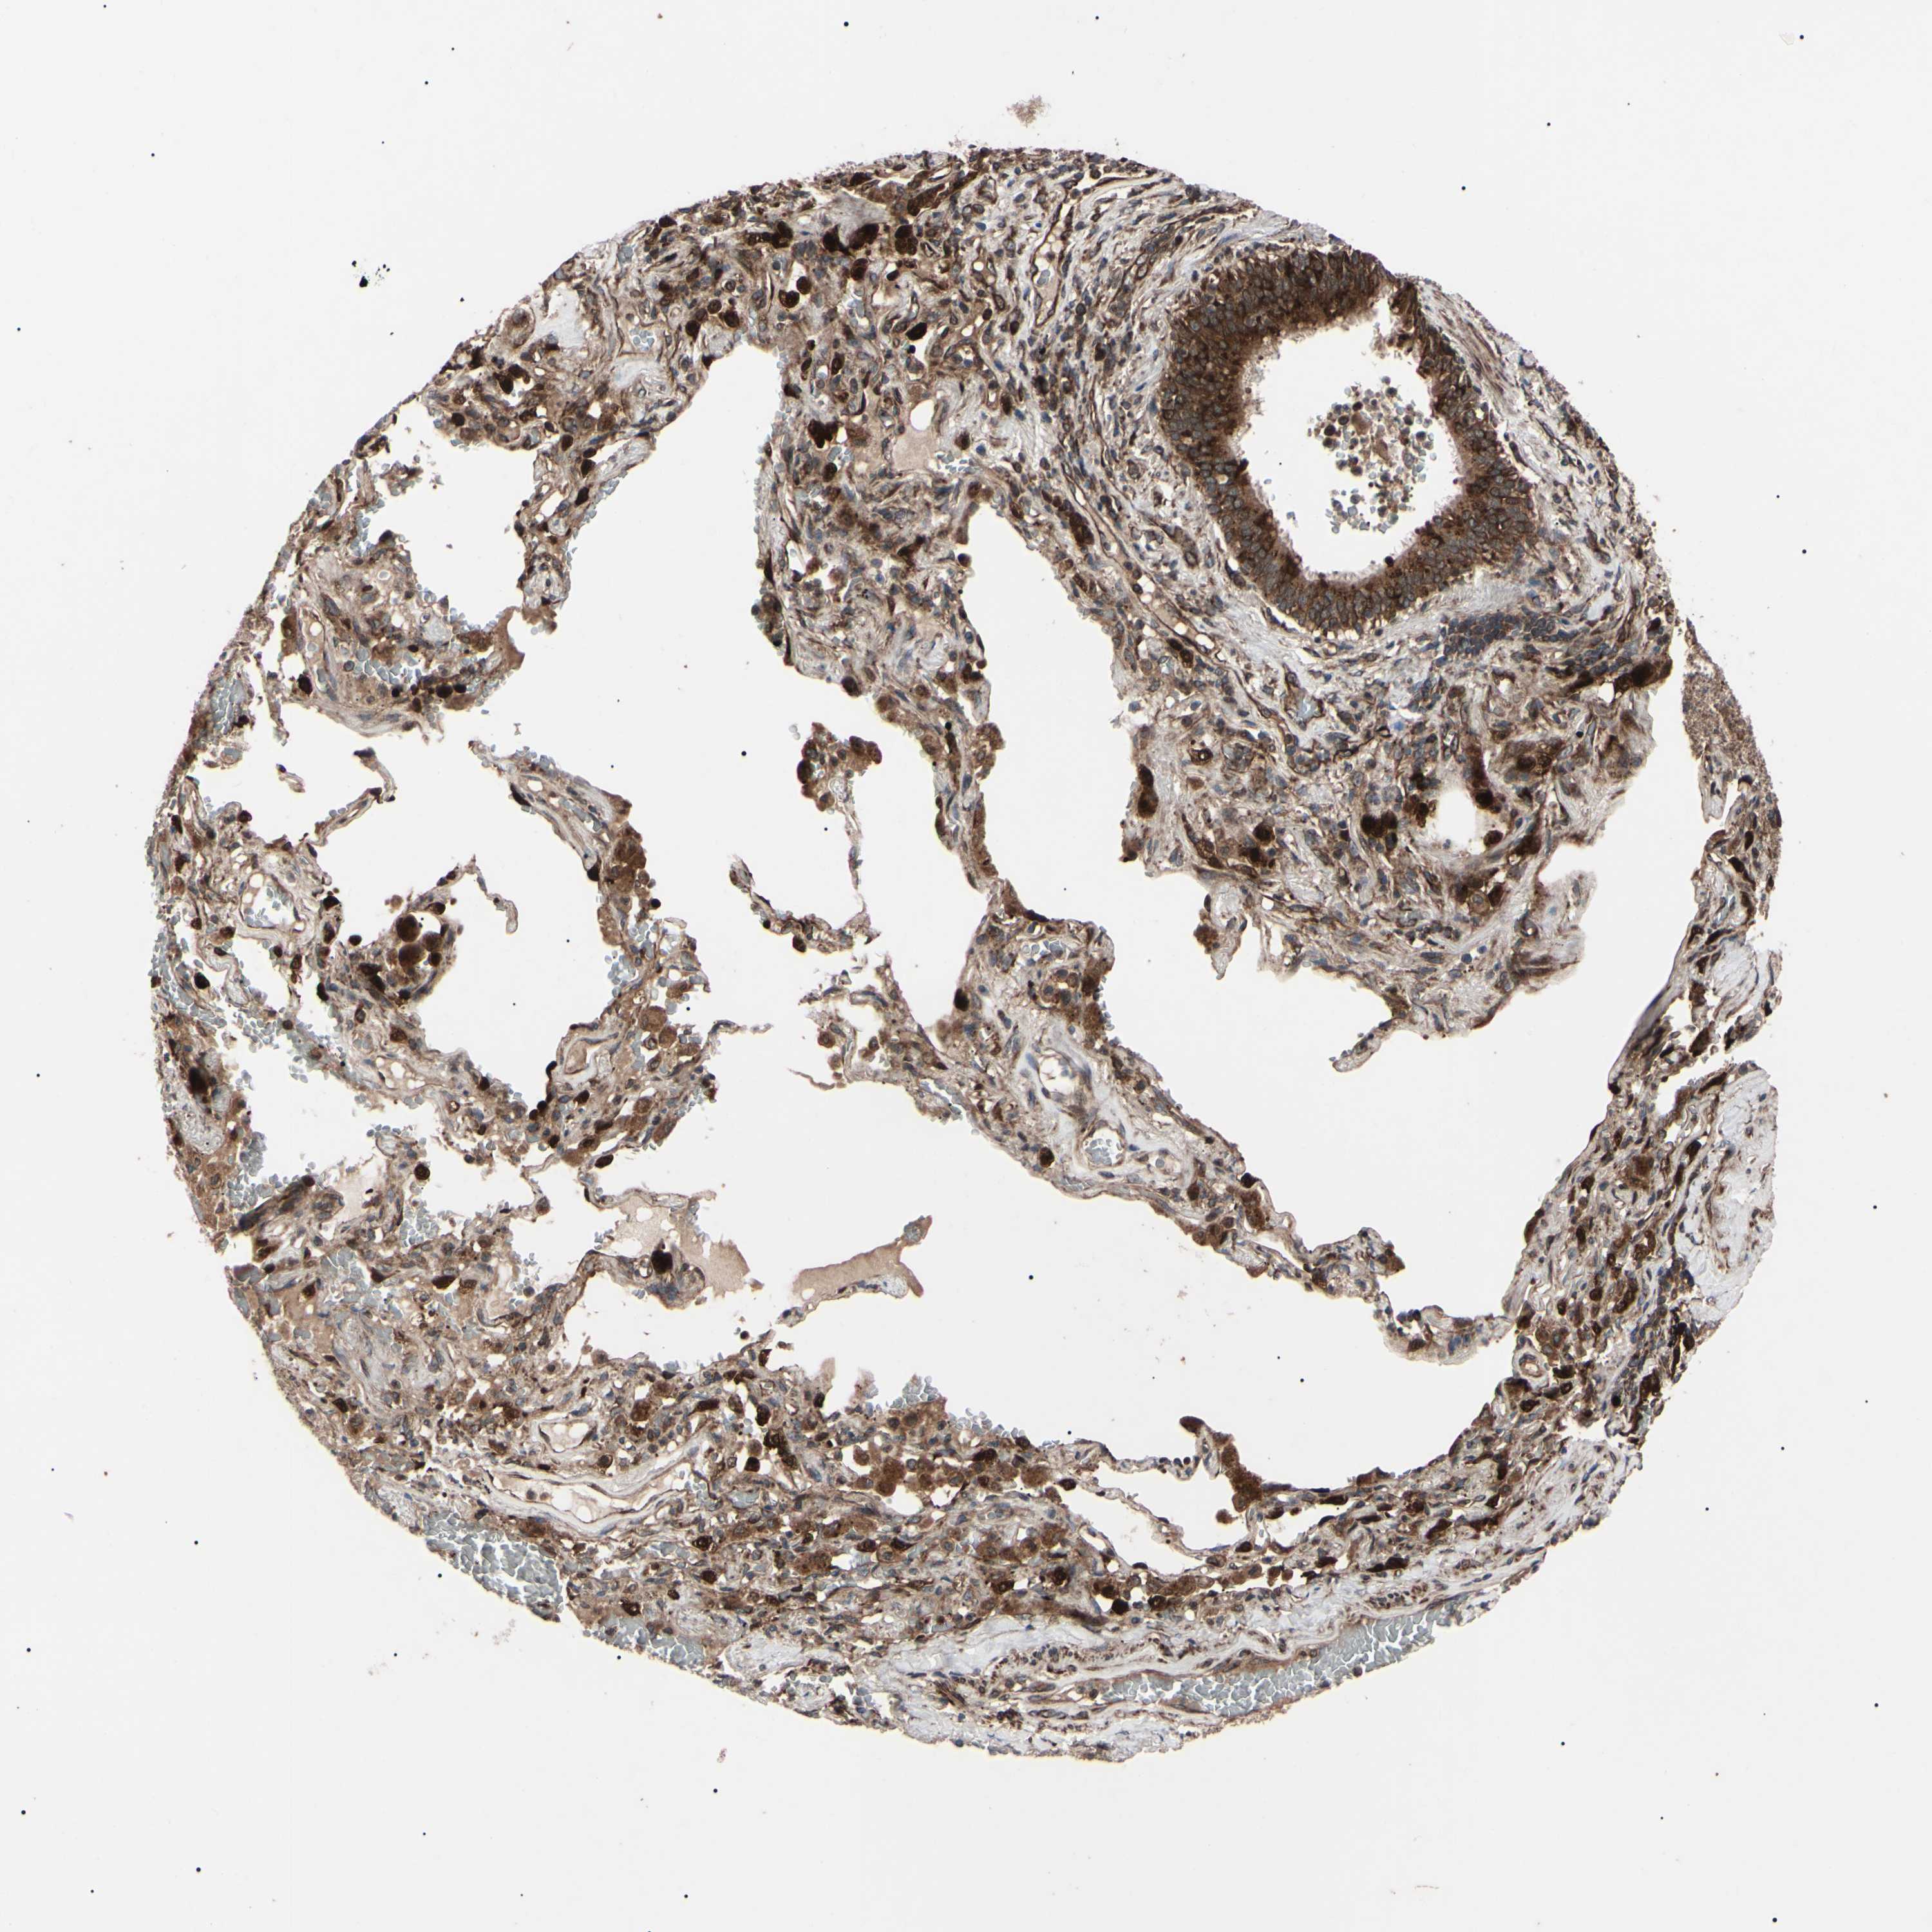

LUNG SQUAMOUS CELL CARCINOMA (TCGA) - Interactive survival scatter ploti

The Survival Scatter plot shows the clinical status (i.e. dead or alive) for all individuals in the patient cohort, based on the same data that underlies the corresponding Kaplan-Meier plots. Patients that are alive at last time for follow-up are shown in blue and patients who have died during the study are shown in red.

The x-axis shows the expression levels (FPKM) of the investigated gene in the tumor tissue at the time of diagnosis. The y-axis shows the follow-up time after diagnosis (years). Both axes are complimented with kernel density curves demonstrating the data density over the axes. The top density plot shows the expression levels (FPKM) distribution among dead (red) and alive patients (blue). The right density plot shows the data density of the survived years of dead patients with high and low expression levels respectively, stratified using the cutoff indicated by the vertical dashed line through the Survival Scatter plot. This cutoff is automatically defined based on the FPKM cutoff that minimizes the p-score. The cutoff can be changed by dragging the vertical line or by entering a cutoff value in the square labeled "Current cut-off".

Under the Survival Scatter plot the p-score landscape (black curve; left axis) is shown together with dead median separation (red curve; right axis). Dead median separation is the difference in median mRNA expression between patients who have died with high and low expression, respectively. It is calculated as follows: median FPKM expression of dead patients with high expression - median FPKM expression of dead patients with low expression. This is intended to aid the user in visually exploring custom cutoffs and the associated p-scores and dead median separation.

Individual patient data is displayed and can be filtered by clicking on one or more of the category buttons on the top of the page. Categories describing expression level and patient information include: high, low, alive, dead, female, male and tumor stages. The scale of the x-axis can be toggled between linear and log-scale by clicking on the "x log" button. Mouse-over function shows TCGA ID, patient information and mRNA expression (FPKM) for each patient.

& Survival analysisi

Kaplan-Meier plots summarize results from analysis of correlation between mRNA expression level and patient survival. Patients were divided based on level of expression into one of the two groups "low" (under cut off) or "high" (over cut off). X-axis shows time for survival (years) and y-axis shows the probability of survival, where 1.0 corresponds to 100 percent.

GUCY1B1 is not prognostic in Lung Squamous Cell Carcinoma (TCGA)

Best expression cut offi

Based on the FPKM value of each gene, patients were classified into two groups and association between prognosis (survival) and gene expression (FPKM) was examined. The best expression cut-off refers the FPKM value that yields maximal difference with regard to survival between the two groups at the lowest log-rank P-value. Best expression cut-off was selected based on survival analysis .

When clicking on this number, the vertical dashed line indicating cut-off, the interactive survival plot, and the Kaplan-Meier curve will be adjusted to show results based on the best expression cut-off.

: 4.01

P scorei

Log-rank P value for Kaplan-Meier plot showing results from analysis of correlation between mRNA expression level and patient survival.

N/A

Average pTPM 7.7

Number of samples 489